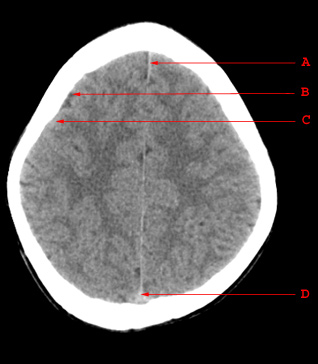

A. Falx Cerebri B. Sulcus C. Gyrus D. Superior Sagittal Sinus

A. Falx Cerebri

B. Sulcus

C. Gyrus

D. Superior Sagittal Sinus